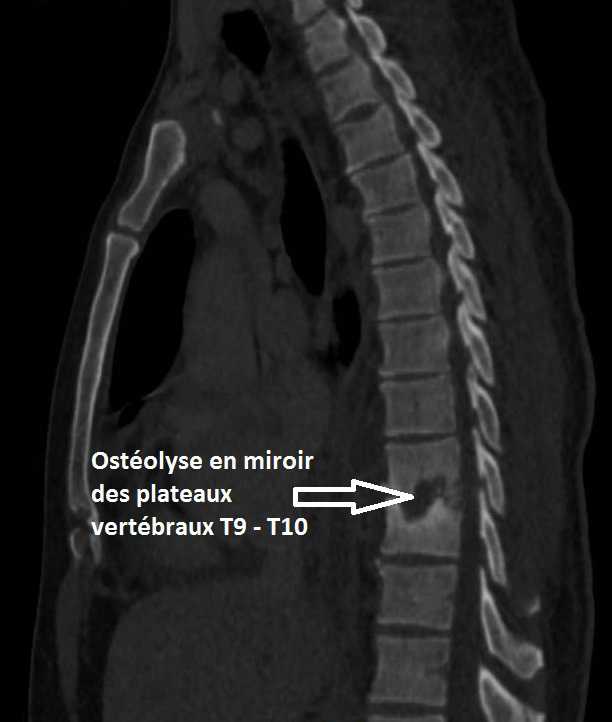

Il faut donc évoquer une pathologie rachidienne inflammatoire/infectieuse/tumorale avec syndrome de compression médullaire partiel se traduisant uniquement par une claudication médullaire : celle-ci correspond à un syndrome pyramidal, démasqué par l’effort.